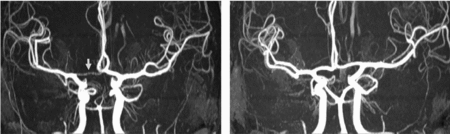

Table 2 shows the concordance and discordance rates of the anterior and posterior CW variants according to the morphological classification. MZ concordance was not higher than DZ concordance in anterior and posterior variants, which presumes the dominance of environmental factors on CW configurations. Figures 3 and 4 show examples of differences in CW configurations in MZ twins.

FIGURE 3 Differences in anterior CW variants of a monozygotic twin pair. Twin A has a right-sided hypoplastic ACA A1 segment (arrow). Twin B has normal anterior CW configuration. ACA = anterior cerebral artery, CW = circle of Willis.